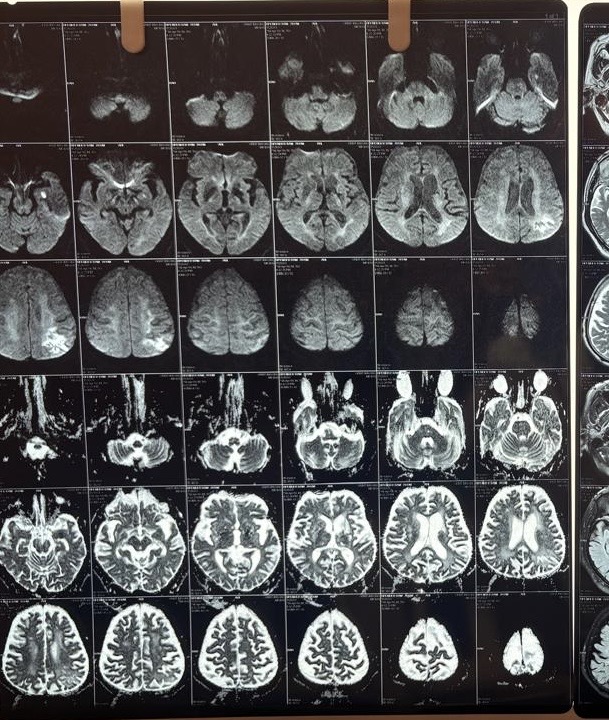

MRI Brain (April 2026)

This was the critical investigation. The MRI brain with DWI (diffusion-weighted imaging), FLAIR, and T2 sequences revealed a layered, complex picture:

Acute ischemic infarct:

A small area of diffusion restriction with low ADC values (a pattern on MRI that indicates fresh, actively dying brain tissue) was identified in the left deep parieto-temporal region, measuring approximately 1.1 x 0.6 cm. This confirmed an acute ischemic stroke (a new blockage of blood supply to a specific brain region) was occurring at or around the time of presentation.

Subacute/chronic left parietal infarct:

A larger heterogeneous T2/FLAIR hyperintense lesion in the left high parietal region (approximately 3.1 x 3.3 cm) showed mixed features: internal gliotic areas with CSF FLAIR suppression, irregular peripheral diffusion restriction with high ADC values, overlying cortical atrophic changes, and subcortical gyriform T1 hyperintensities. This pattern was consistent with sequelae of a subacute to chronic prior infarct with cortical laminar necrosis (scarring of the cortical surface following prolonged ischemia))*; indicating a prior stroke that had likely gone undiagnosed.

Old lacunar infarcts:

Multiple small gliotic lacunar infarcts (tiny old stroke scars from small vessel disease) were seen bilaterally in the corona radiata and ganglio-capsular regions, the largest approximately 7.7 x 2.8 mm in the left anterior ganglio-capsular region.

White matter disease:

Bilateral periventricular and centrum semiovale T2/FLAIR hyperintense white matter foci without diffusion restriction, consistent with chronic microvascular ischemic changes (long-standing small vessel damage due to diabetes and hypertension).

Cerebral and cerebellar atrophy:

Diffuse senile atrophy (age-related brain shrinkage) was noted across both cerebral hemispheres, most prominent in the fronto-parietal regions, along with mild cerebellar atrophy. This contributed to the cognitive picture.

The brainstem, basal ganglia, thalami, internal capsules, major intracranial vessels (flow voids), and cerebellopontine angles were all intact.